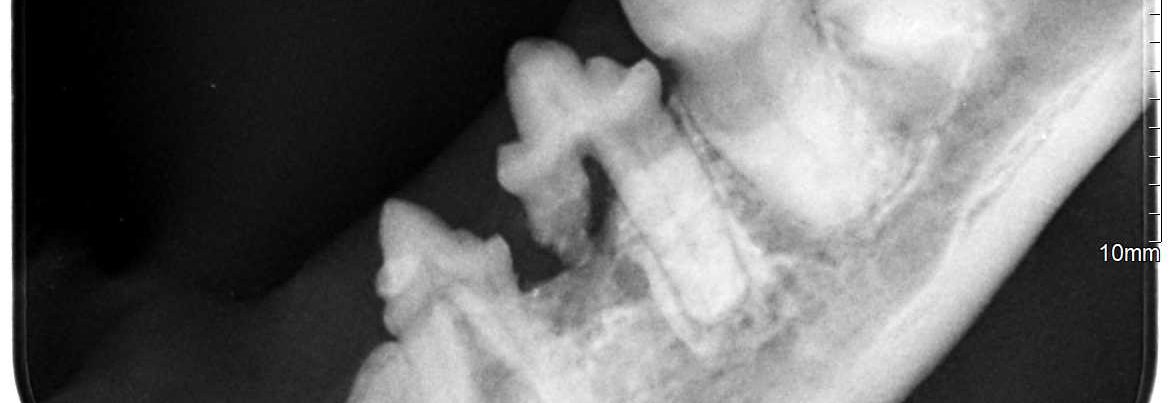

Digitales Röntgen

Die Röntgendiagnostik ist ein unverzichtbares bildgebendes Verfahren sowohl in der inneren Medizin als auch in der Orthopädie.

Wir arbeiten mit einem digitale Röntgengerät der Firma Examion. Mit diesem Gerät können wir aufgrund der hohen kw-Leistung und der damit verbundenen kurzen Belichtungszeiten Röntgenbilder vom Zwergkaninchen bis hin zum Bernhardiner in gleichbleibend guter Qualität anfertigen. Unser Röntgentisch mit Schwimmplatte und die 605 vorprogrammierten Organprofile ermöglichen uns und Ihrem Vierbeiner eine stressfreie und schnelle Anfertigung benötigter Röntgenaufnahmen.

Aufgrund der digitalen Technik werden die Bilder innerhalb kurzer Zeit direkt auf dem Monitor dargestellt und müssen nicht erst noch entwickelt werden. Das verkürzt die Untersuchungszeit und ermöglicht es uns, Ihnen die Röntgenbilder als CD, E-Mail zukommen zulassen.